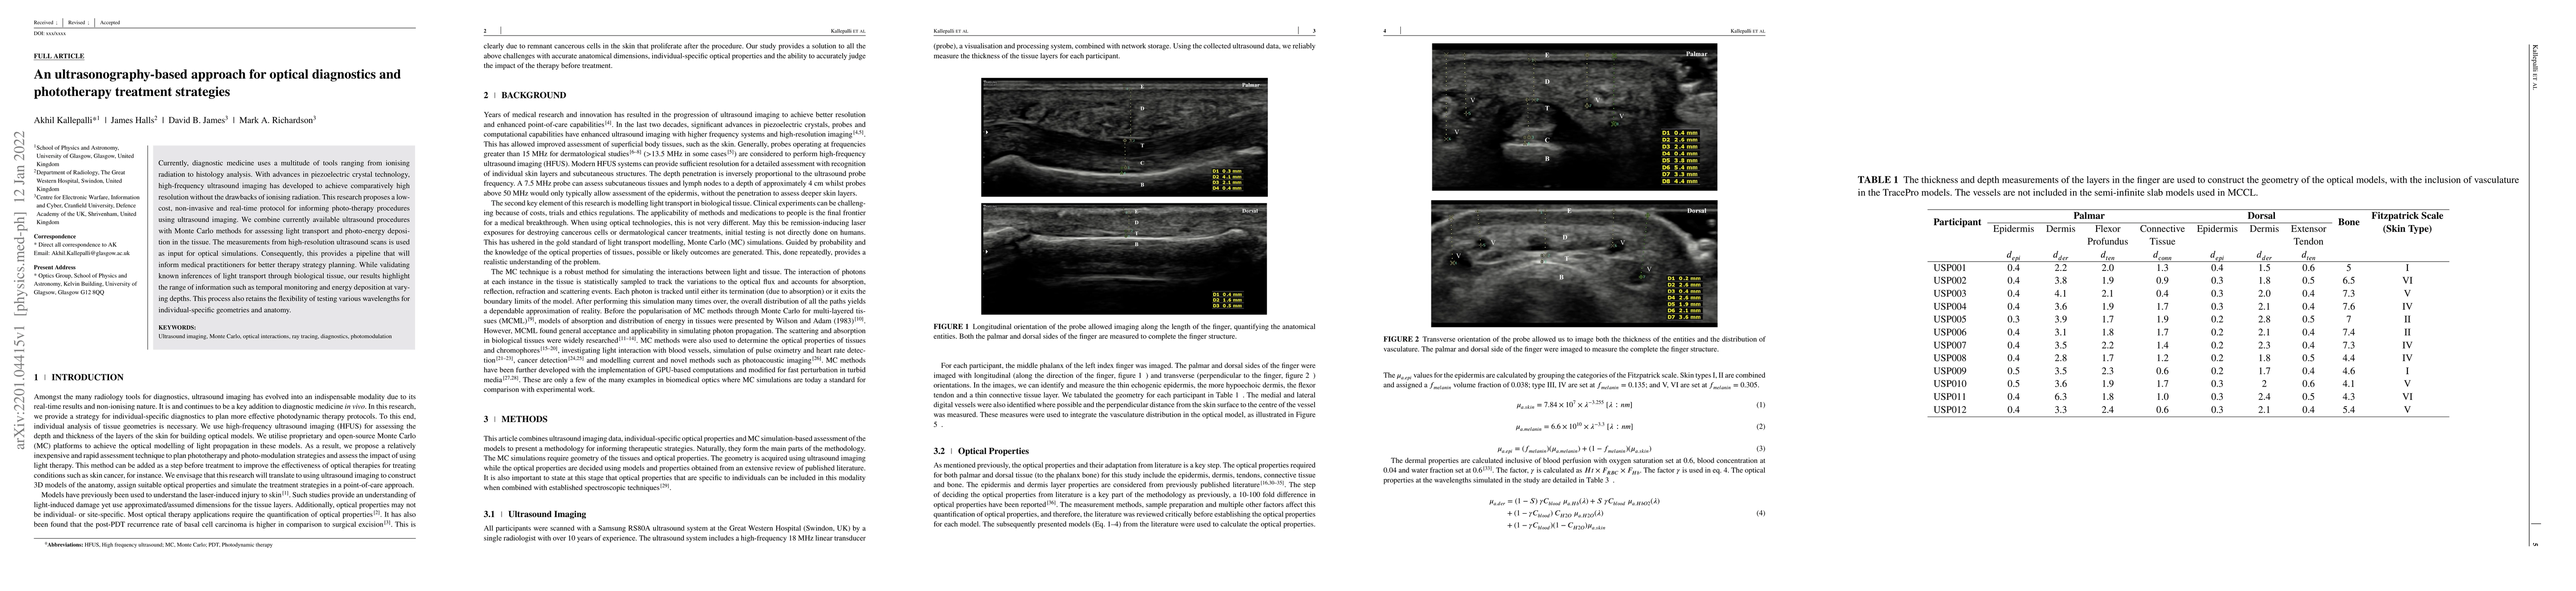

An ultrasonography-based approach for optical diagnostics and phototherapy treatment strategies

Currently, diagnostic medicine uses a multitude of tools ranging from ionising radiation to histology analysis. With advances in piezoelectric crystal technology, high-frequency ultrasound imaging h...